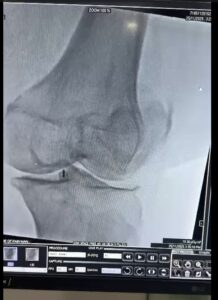

Joint Health: Core Tests, Imaging and Scans

Important tests include:

• Vitamin D levels

• Inflammatory markers (CRP, ESR)

• Thyroid profile

• Rheumatoid factor (if indicated)

• DEXA scan for bone mineral density

The DEXA scan measures bone density.

T-score between -1.0 and -2.5 = Osteopenia

Below -2.5 = Osteoporosis